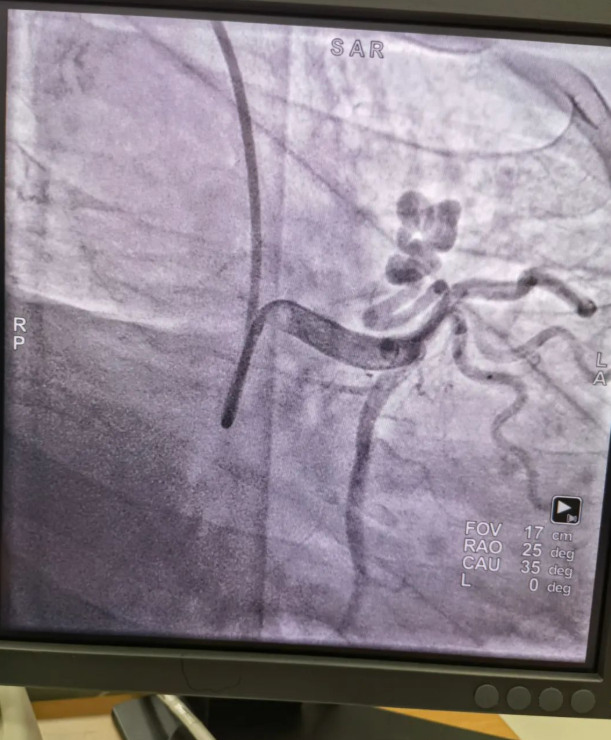

不久前,來自新疆的患者石先生去年至今反復(fù)胸悶、氣短、胸痛,就診于新疆某院,懷疑“冠心病”,住院行冠狀動(dòng)脈造影術(shù),石先生造影提示“冠狀動(dòng)脈肺動(dòng)脈瘺”,而他并非“冠心病”,所以給予的“冠心病”治療,效果不佳。出院后仍反復(fù)出現(xiàn)胸痛、胸悶、氣短等癥狀,經(jīng)親友介紹了解到西安國際醫(yī)學(xué)中心醫(yī)院心臟病醫(yī)院心臟內(nèi)科二病區(qū)曾廣偉主任,多年來潛心研究心臟病介入治療,成功主刀救治了許許多多高危復(fù)雜病例,尤其是在先心病及結(jié)構(gòu)性心臟病封堵,以及冠心病、心律失常射頻消融及起搏治療等方面積累了豐富的診療經(jīng)驗(yàn)。

此病例罕見,在曾廣偉從醫(yī)18年生涯里曾碰到有2個(gè)印象深刻的病例,患者分別是53歲和66歲,當(dāng)時(shí)建議患者入院進(jìn)行動(dòng)脈瘺的封堵術(shù),但患者和家屬考慮到這個(gè)手術(shù)案例極少,風(fēng)險(xiǎn)也高,均未接受手術(shù)治療建議,只是能采取藥物保守治療,出院后隨訪得知患者癥狀緩解效果不佳,后來在隨訪中也與53歲患者失去了聯(lián)系,而66歲患者因冠狀動(dòng)脈肺動(dòng)脈瘺出現(xiàn)反復(fù)心衰,在當(dāng)?shù)蒯t(yī)院藥物治療,短短2年時(shí)間,患者因?yàn)閯?dòng)脈瘺未及時(shí)手術(shù)失去了生命。所以此次患者石先生到訪,曾廣偉主任在詳細(xì)掌握病例資料基礎(chǔ)上,果斷建議進(jìn)行動(dòng)脈瘺的封堵術(shù)治療,為了提高手術(shù)成功率和精準(zhǔn)度,曾廣偉主任搜集相關(guān)診療資料,反復(fù)推演論證,經(jīng)過相當(dāng)充足的準(zhǔn)備工作,于5月18日成功進(jìn)行了封堵手術(shù),完全堵上了瘺口。

患者術(shù)后第2天,已經(jīng)沒有明顯的胸悶、氣短、胸痛等癥狀,目前身體狀態(tài)良好。本次手術(shù)曾廣偉主任及其團(tuán)隊(duì),采取從右手臂一根血管進(jìn)入,并在2小時(shí)之內(nèi)完美封堵,創(chuàng)口小,痛苦小。手術(shù)雖然難度大、風(fēng)險(xiǎn)高,相關(guān)案例也少,但是曾廣偉主任主刀即在巔峰,這樣一臺(tái)完美的手術(shù)靠的不是運(yùn)氣,是豐富的臨床手術(shù)經(jīng)驗(yàn),扎實(shí)的專業(yè)知識(shí)儲(chǔ)備,以及對(duì)醫(yī)療事業(yè)的孜孜追求。

冠狀動(dòng)脈瘺是指冠狀動(dòng)脈與心腔、冠狀靜脈、肺動(dòng)脈等的異常連接,是一種少見的先天性心臟病,發(fā)病率為1.3%。而冠狀動(dòng)脈肺動(dòng)脈瘺是冠狀動(dòng)脈與肺動(dòng)脈之間產(chǎn)生的一種血管性瘺口,導(dǎo)致冠狀動(dòng)脈里的血液流入肺動(dòng)脈里,使冠狀動(dòng)脈里血液流量減少,出現(xiàn)心肌供血不足,冠狀動(dòng)脈肺動(dòng)脈瘺會(huì)使患者出現(xiàn)胸部疼痛、胸悶、呼吸困難、頭暈、乏力等一系列癥狀,隨著疾病不斷進(jìn)展,可引發(fā)心功能的障礙和心肌缺血,肺動(dòng)脈會(huì)逐漸形成肺動(dòng)脈高壓,還可能導(dǎo)致動(dòng)脈瘤的破裂,甚至威脅病人的生命安全,所以早期發(fā)現(xiàn)和治療冠狀動(dòng)脈肺動(dòng)脈瘺,對(duì)病人的預(yù)后改善具有重要的意義。